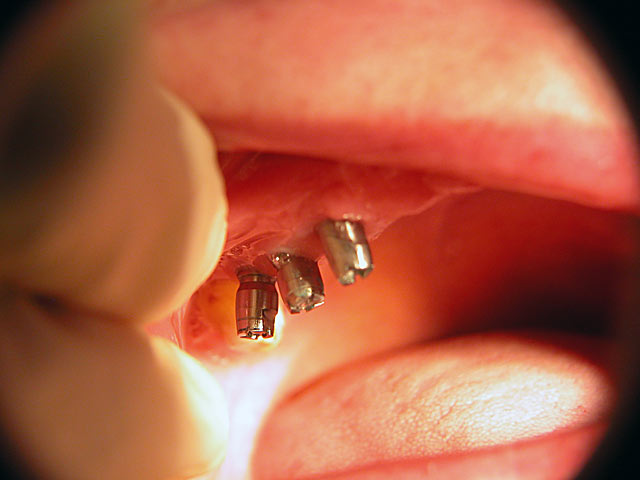

Kugelkopf-Implantation: